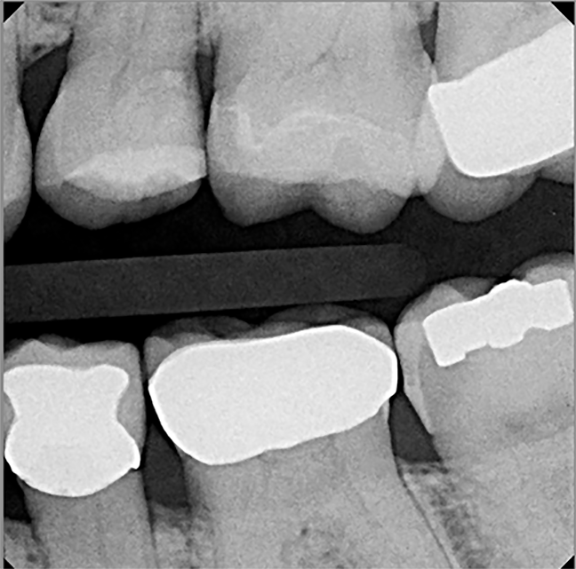

Fig 8. A vertical bitewing radiograph of tooth No. 13 after the restoration is completed. The tooth will be monitored clinically and radiographically for symptoms over the next 12 months to determine if root canal therapy will ultimately be necessary.

Figure 8